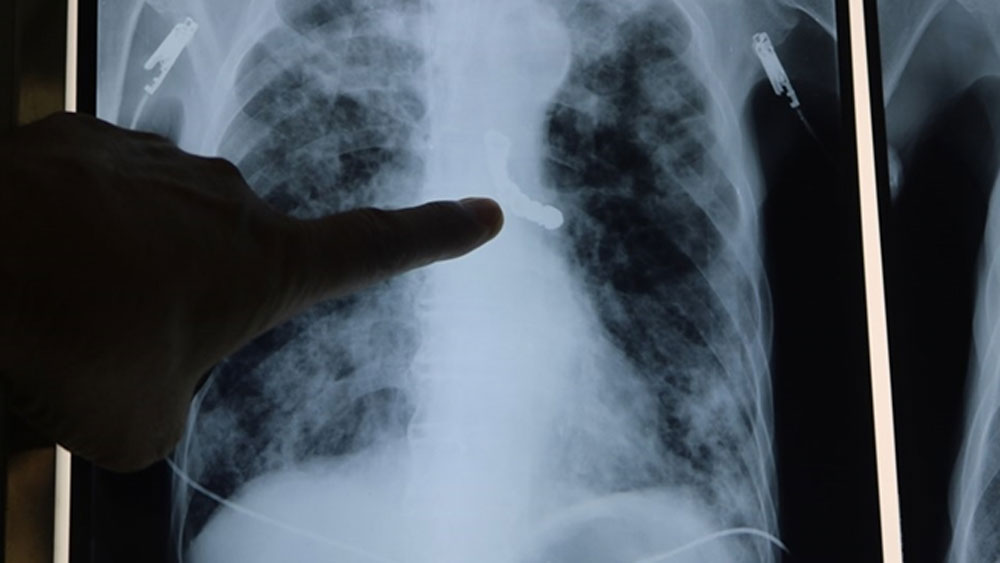

Hình ảnh ăng giả rơi vào phế quản gốc bên trái. |

Trước đó, trong quá trình nằm viện để điều trị di chứng do tiền sử lao phổi, trong một cơn ho khạc đờm mạnh, toàn bộ hàm răng giả của cụ bị rơi và mắc kẹt vào khí phế quản gốc bên trái, gây tắc nghẽn đường thở và đe dọa tính mạng.

Cụ N.T không phải là trường hợp hy hữu đầu tiên. Năm 2018, Bệnh viện Phổi Trung ương cũng tiếp nhận một cụ ông bị rơi một hàm gồm 4 chiếc răng vào phế quản, năm nay trường hợp này bị tới 9 chiếc răng sứ kim loại với chiều dài lên tới gần 5 cm nên quá trình nội soi lấy dị vật phức tạp hơn, đòi hỏi các chuyên gia nội soi nhiều kinh nghiệm.